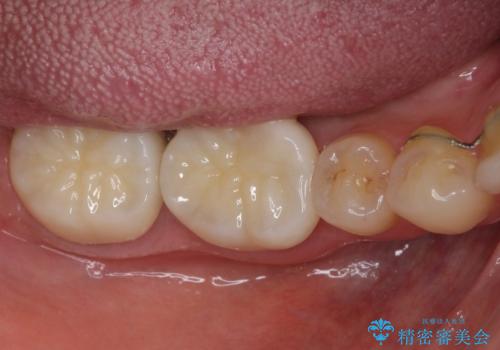

- 前歯の隙間と奥歯の目立つ銀歯を気にして来院された患者様です。

インビザラインにより下顎前歯の隙間を閉じるとともに、奥歯の咬み合わせを改善させることとしました。

矯正治療後には、銀歯のクラウンをセラミッククラウンへ替える補綴治療を行うこととしました。